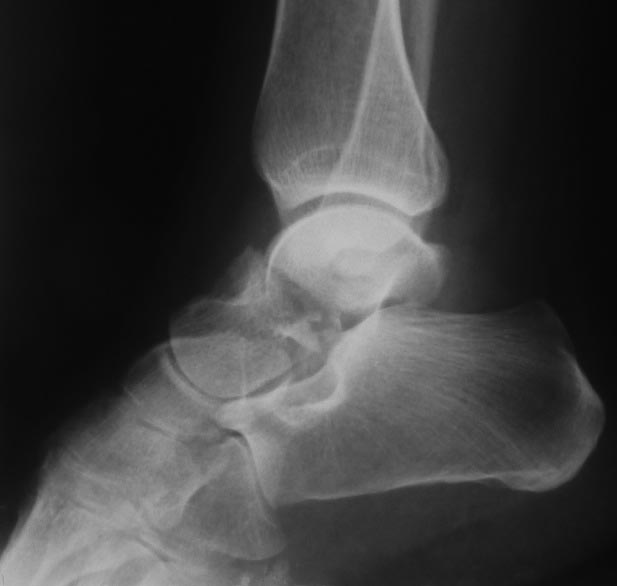

Коллеги! Делюсь первым опытом такой операции Два месяца назад потупил пациент с оскольчатым переломом таранной кости, после ДТП. При поступлении налажено скелетное вытяжение. Ниже рентгенограммы при поступлении

Вопрос стоял об открытой операции с остеотомией наружной лодыжки, но решили попробовать артроскопию.